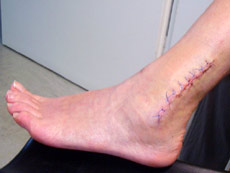

Für die nächsten sechs Wochen sind Rollstuhl und Krücken angesagt...